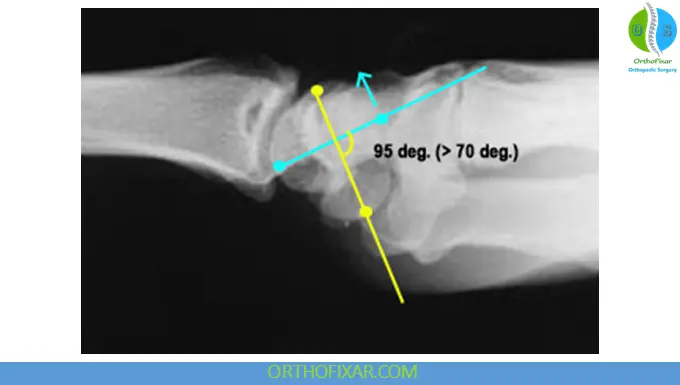

3. Increased Scapholunate Angle

- Angle >70° on lateral view

- Associated with Dorsal Intercalated Segment Instability